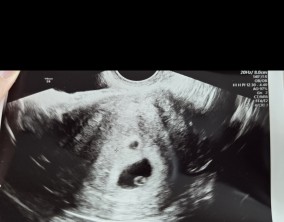

눈물로 실감한 아홉 번째 주